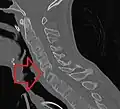

X-ray showing bamboo spine in a person with ankylosing spondylitis

CT scan showing bamboo spine in ankylosing spondylitis